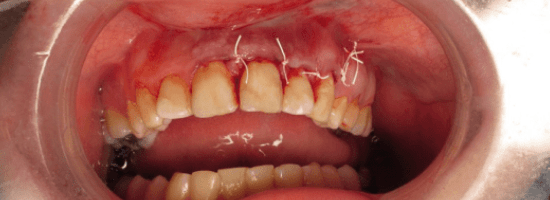

Crown Lengthening

A surgical procedure done to expose more of the tooth structure by reshaping or removing gum and bone tissue. It’s usually performed when a tooth is too short to hold a crown properly.